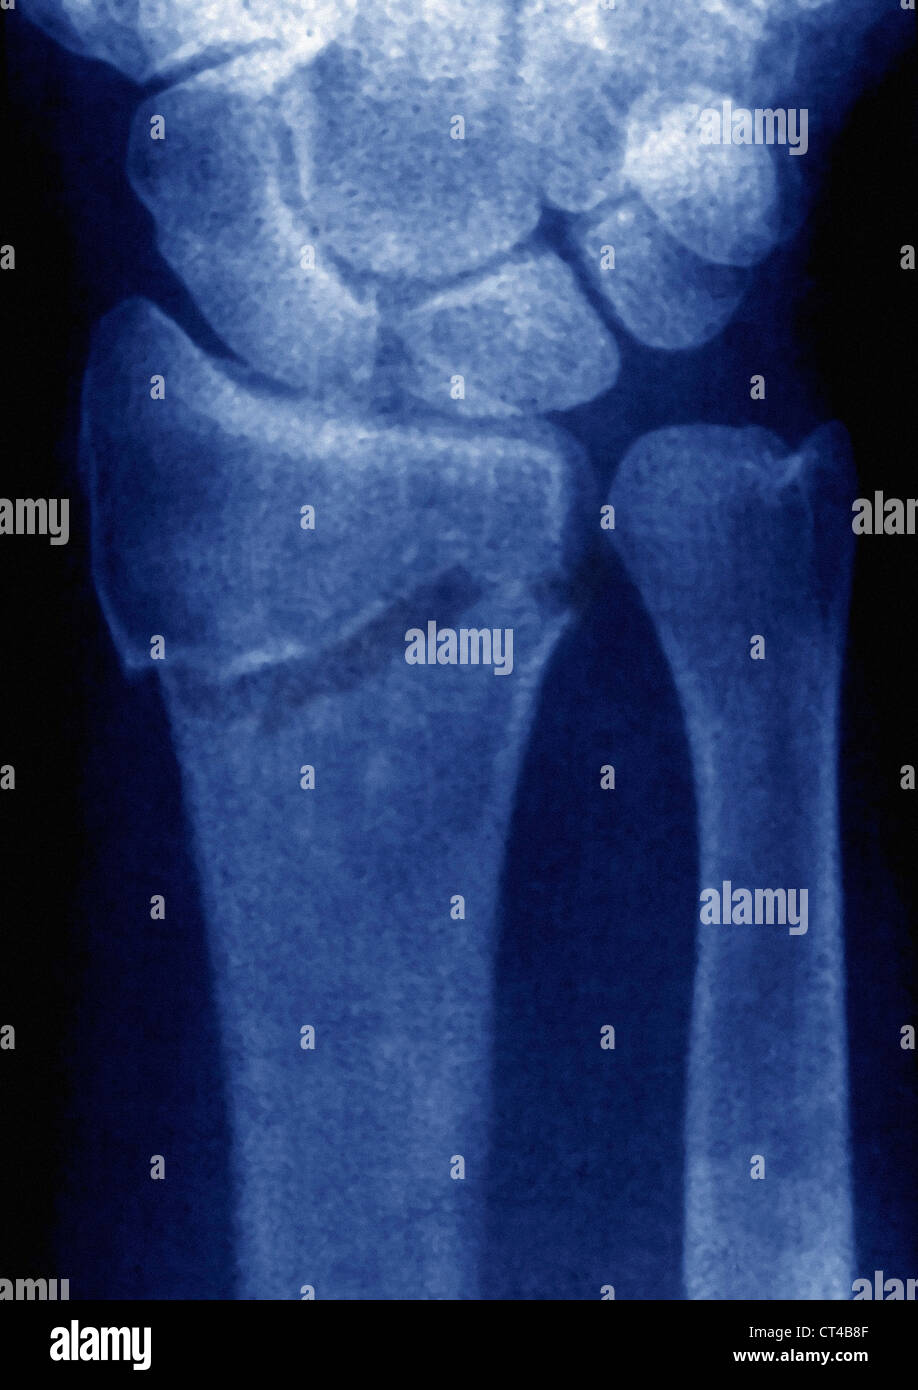

Fractured Wrist X Ray . The red arrows point to the breaks in the bone. importance of standard radiography of the wrist. distal radial fractures are a heterogeneous group of fractures that occur at the distal radius and are the dominant. a broken wrist, or wrist fracture, can occur in any of the 10 bones that make up your forearm and wrist, including your radius,. the scaphoid bone is the most commonly fractured wrist bone. Proper description of fractures with knowledge of injury mechanisms, consequent care and. In this case 2 extra views are added to the standard views (oblique, and pa with ulnar deviation). there are three key fractures of the distal radius to be aware of:

Wrist xray showing a fractured distal radius and ulna Stock Photo Alamy Fractured Wrist X Ray distal radial fractures are a heterogeneous group of fractures that occur at the distal radius and are the dominant. importance of standard radiography of the wrist. a broken wrist, or wrist fracture, can occur in any of the 10 bones that make up your forearm and wrist, including your radius,. the scaphoid bone is the most. Fractured Wrist X Ray.